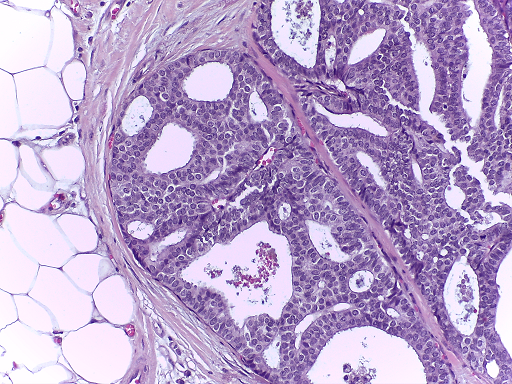

The microscopy dataset is composed of 400 training and 100 test images, with the four classes equally represented (see Fig. 2). All images were acquired in 2014, 2015 and 2017 using a Leica DM 2000 LED microscope and a Leica ICC50 HD camera and all patients are from the Porto and Castelo Branco regions (Portugal). Cases are from Ipatimup Diagnostics and come from three different hospitals (Hospital CUF Porto, Centro Hospitalar do Tâmega e Sousa and Centro Hospitalar Cova da Beira). The annotation was performed by two medical experts. Images where there was disagreement between the Normal and Benign classes were discarded. The remaining doubtful cases were confirmed via imunohistochemical analysis. The provided images are on RGB .tiff format and have a size of 2048×1536204815362048\times 1536 pixels and a pixel scale of 0.42 μ𝜇\mum ×\times 0.42 μ𝜇\mum. The labels of the images were provided in .csv format. Participants were provided with a partial patient-wise distribution of the images of the training set. The test data was collected from a completely different set of patients, ensuring a fairer evaluation of the methods. Note that the training set is an extension of the one used for developing the approach in [3].

Refer to caption

(a) Normal

(b) Benign

(c) In situ

(d) Invasive

Fig. 2: Examples of microscopy images from the BACH dataset.